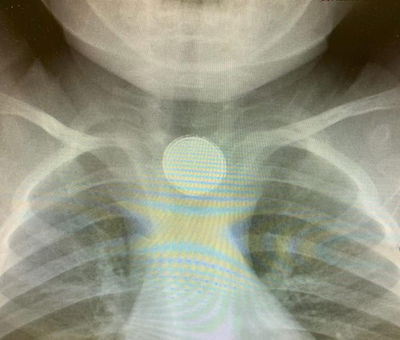

ילדה בת 3 הגיעה לבית החולים, לאחר שטבעת עמה שיחקה נתקעה לה בוושט. הרופאים שחששו מקצוותיה חדים, העבירו את הילדה לחדר הניתוח, והצליחו להוציא את הטבעת (בארץ)